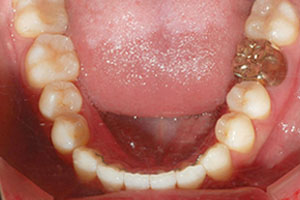

치료증례 전후사진

Before & After